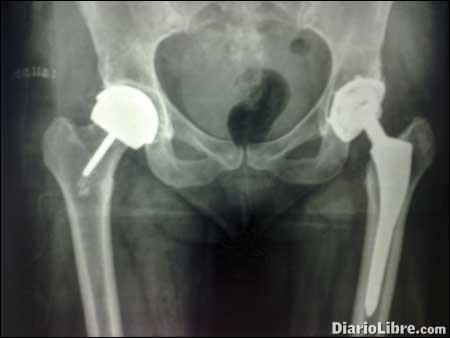

Un reemplazo articular no es más que la sustitución de una articulación dañada, el lugar donde dos o más huesos se unen (como la rodilla y cadera) por un material artificial llamado prótesis.

La prótesis de las caderas -segunda más frecuente- se reemplaza por dos causas: traumas o por artrosis. Para esto los pacientes tienen que ser sometidos a un tratamiento de esteroides por mucho tiempo. Existen otros factores de riesgos como lo es la edad (personas con 65 y 75 años también pasan por el proceso).

Los pacientes empiezan el proceso realizando una radiografía simple, puestos de pie.